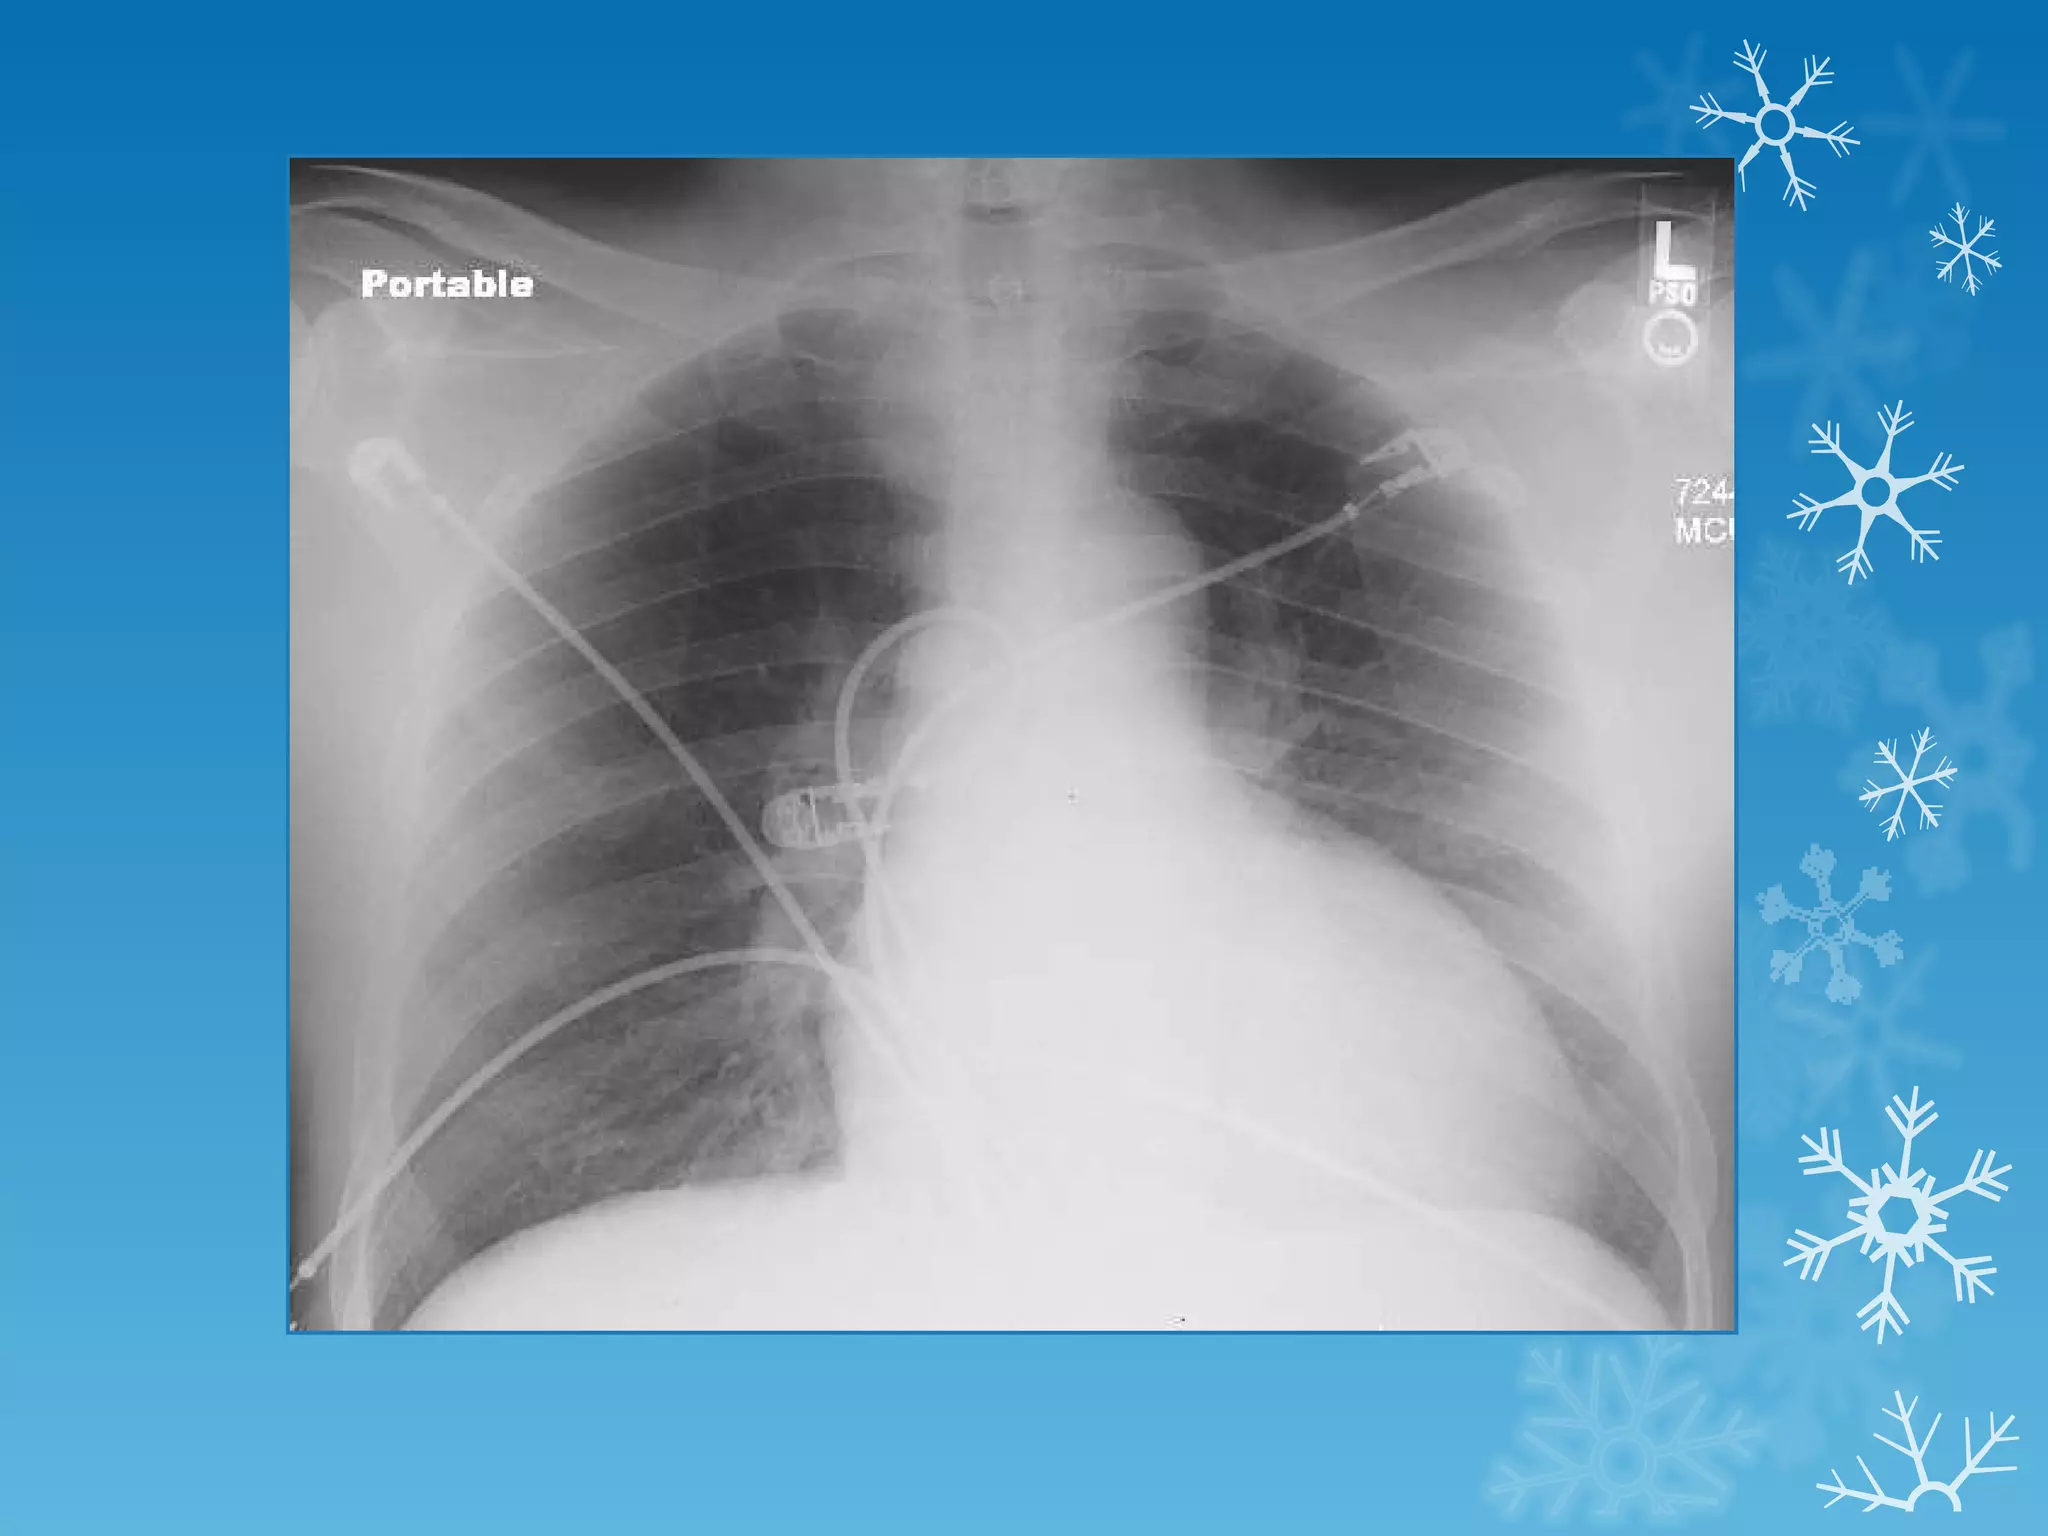

This document discusses chest x-ray interpretation and provides guidance on evaluating x-rays. It explains that tissue density determines how an x-ray beam penetrates, with denser tissues appearing whiter and less dense tissues appearing blacker. It also outlines different chest x-ray views and factors to consider like patient orientation, age, gender, and rotation. Abnormalities are described as appearing too white, too black, too large, or in the wrong place. The document stresses a systematic approach of identifying, localizing, describing lesions, and providing differential diagnoses.